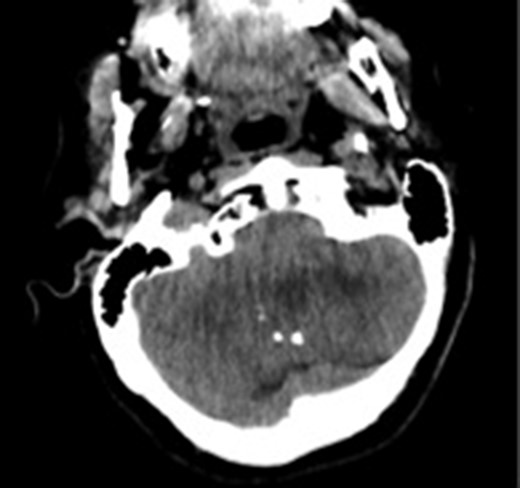

Computed tomography image showing calcifications in the lesion. The margins of the lesion cannot be differentiated from cerebellar parenchyma.